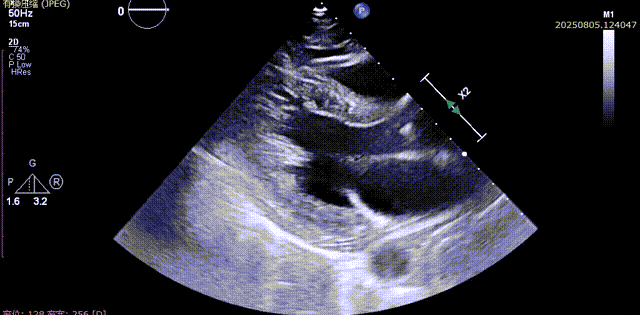

术前胸骨旁长轴切面可见流出道结构良好,五腔心切面可见主动脉瓣少中量反流

流出道结构观察

五腔心切面观察

脱钩后输送器部分回收,瓣膜无位移及形变,确认瓣膜完全脱钩,回撤输送系统及导丝,超声再次评估,瓣膜位置及形态良好,无明显瓣周漏,峰值流速2.44m/s,平均压差13mmHg,患者未诉不适,入路缝合后返回病房

胸骨旁长轴评估